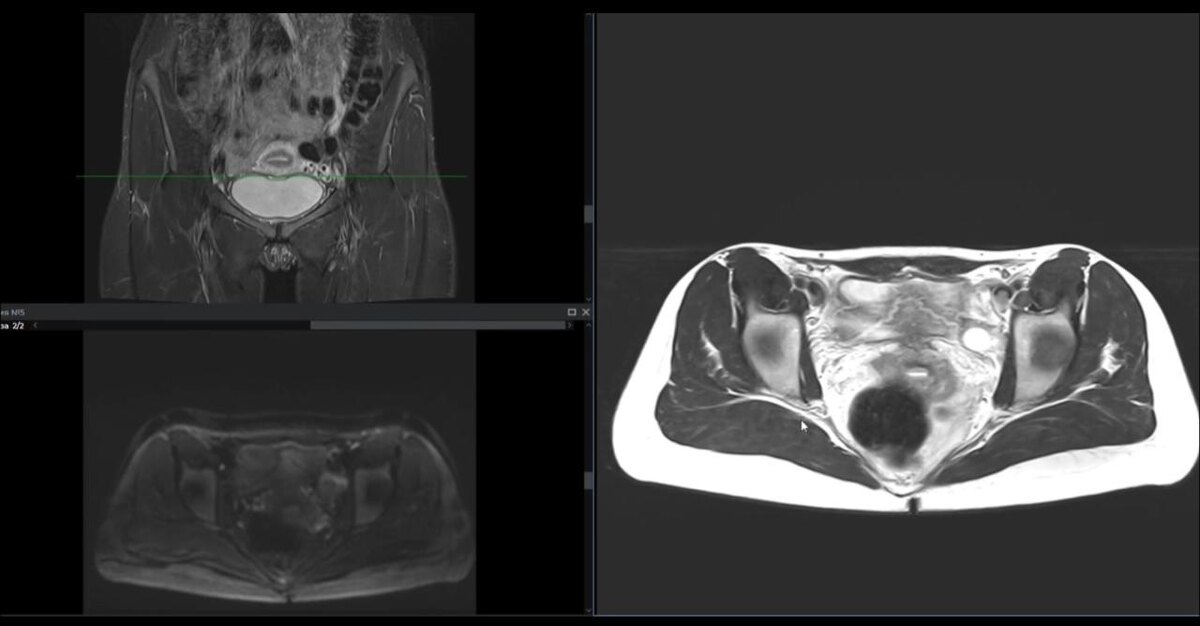

МРТ малого таза женского

МРТ малого таза – это не инвазивное высокоинформативное исследование, позволяющее визуализировать органы малого таза - половые органы, мочевой пузырь, прямую кишку, локальные кровеносные сосуды и лимфатические узлы, а также некоторые кости таза. Данное исследование позволяет врачу обнаружить патологические изменения (воспалительной, опухолевой и другой природы), поставить правильный диагноз и назначить лечение.

МРТ позволяет визуализировать нормальную анатомию, структуры малого таза женщины и их патологические изменений.

Специально настроенный протокол сканирования соответствует мировым стандартам МР-визуализации, в том числе включает использование программы для динамического контрастирования с возможностью применения современные классификаций при стадировании и/или локализации патологических изменений.